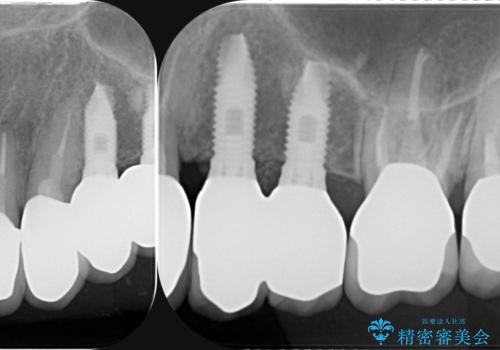

虫歯による歯の喪失 インプラントによる咬合機能回復

虫歯の徹底的な除去、安定した噛み合わせを達成するインプラント治療、深い虫歯、根管治療といった複数の治療項目を一つづつ積み重ね、長期的な予後を目指します。

複雑な問題点に対する明確な治療目標を立てることで、最終的に長い予後を期待できる治療を達成することができます。